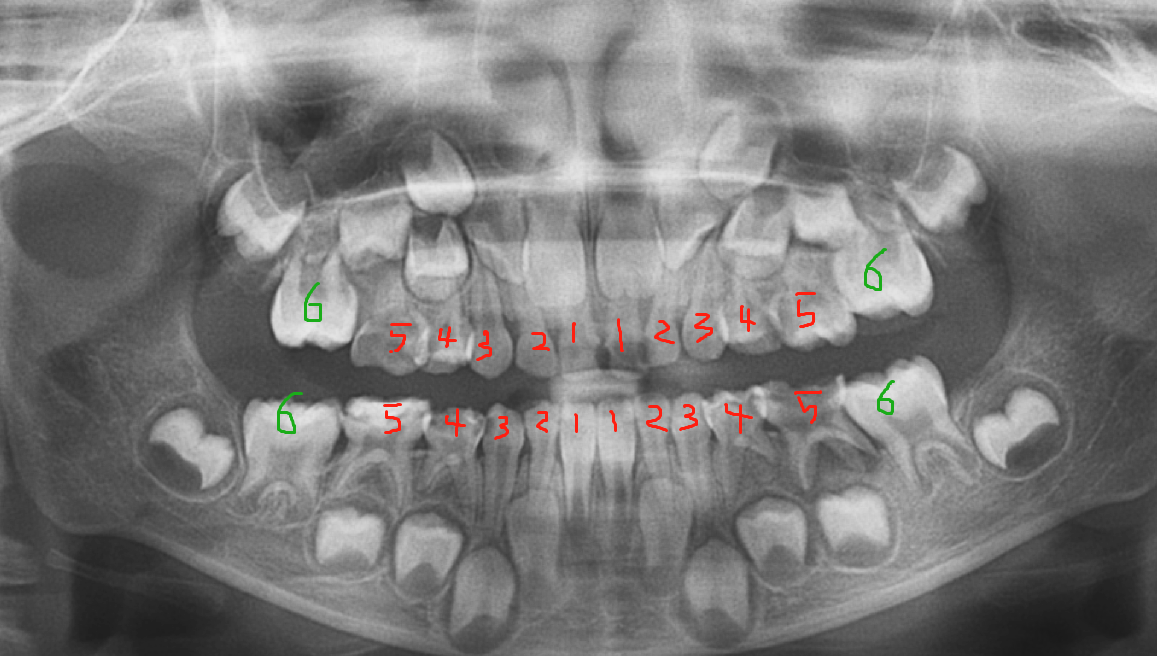

六岁左右,开始长六龄齿,加上四颗六龄齿,孩子的牙齿是24颗。(下图为六岁小孩全景片)